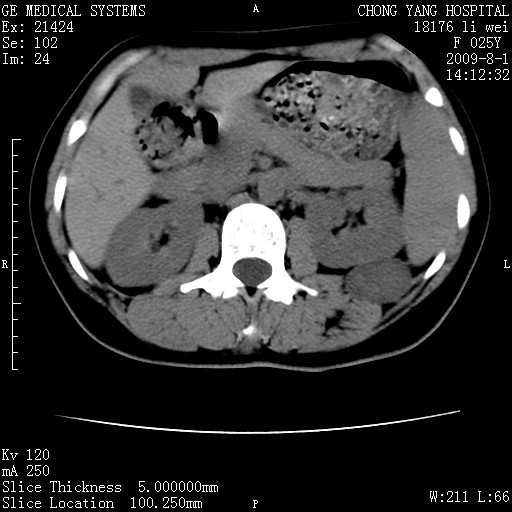

以下是引用拾荒者在2009-12-30 21:45:00的发言:[br]ct21383:神经纤维瘤病( nf) [br] [br] 神经纤维瘤病。四肢都有,影响美观,四肢上的手术了。[br] [br] [br]谢谢!